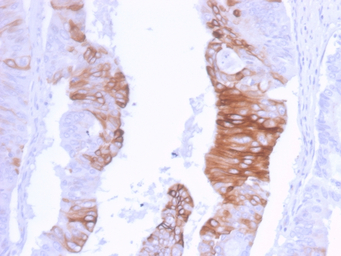

IHC-P analysis of human colon carcinoma section using GTX02660 Cytokeratin 20 antibody [KRT20/3129R].

IHC-P analysis of human colon tissue section using GTX02660 Cytokeratin 20 antibody [KRT20/3129R].